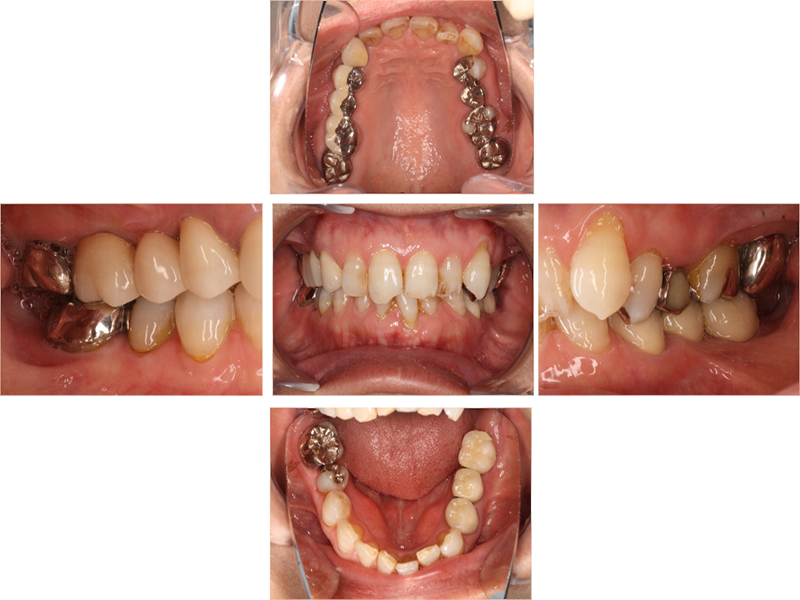

初診時口腔内写真

初診時X線写真